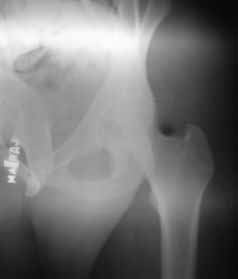

Male 22 yrs of age, RTA, front seat passenger in a truck. Sustained grade IIIB fracture of Tibia, and a Posterior dislocation of the Ipsilateral Left Hip.

Emergent closed reduction performed, and Tibial wound debrided. Next day Exfix applied and fibula plated. Initially femoral head fracture was not appreciated and it was thought that this is a posterior wall fracture. Presently two weeks down the line, Tibial wound is better but not completely healthy. and plastics want to wait for another five days, before they flap it. I enclose radiographs, Judet view, Ct scans in this and following mails.

2)The femoral head fracture involves the anter-inferior part and not the weight bearing superior dome. Also while moving the hip after taking weight off the traction, it does seem pretty stable. Should it be fixed even then?

Based on the selected images that you shared with us, I would not leave it as is. The fragment is significant in terms of its size and location and displacement.